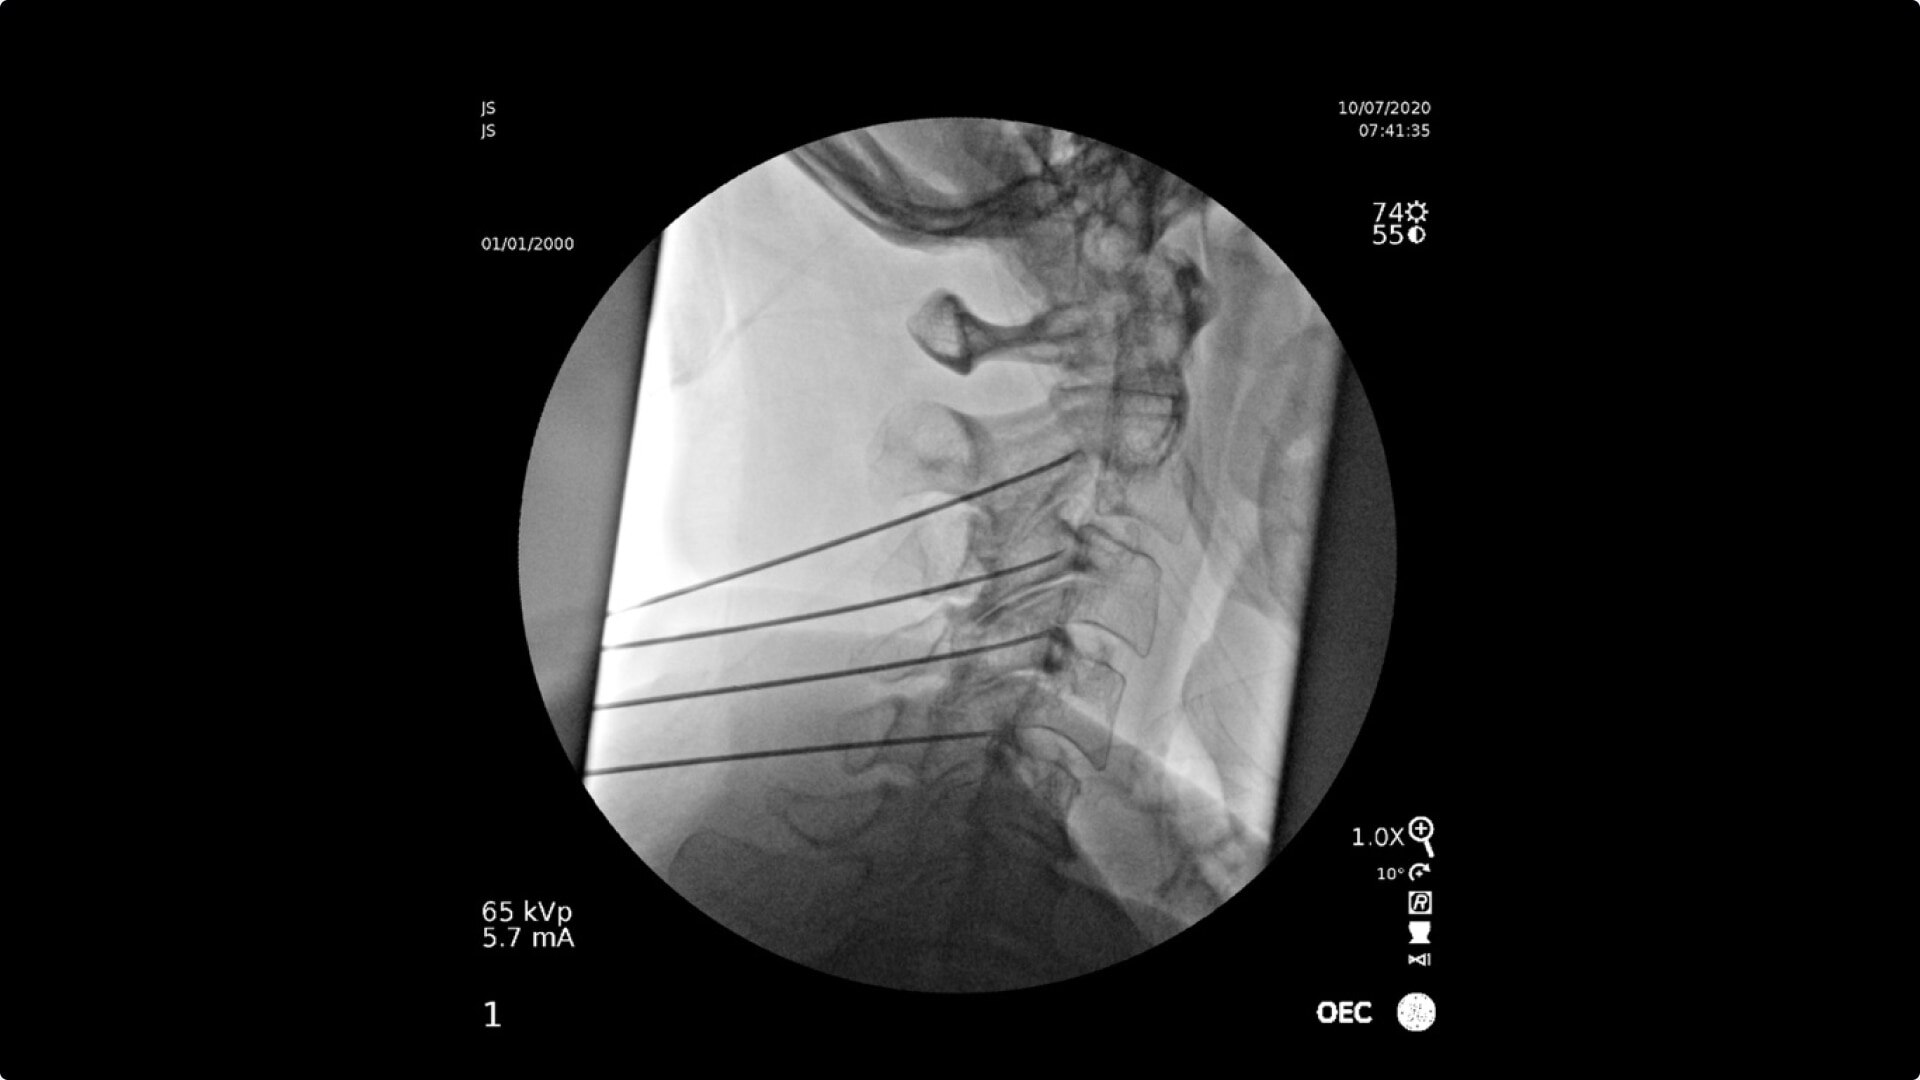

Consistently experience amazing image quality, precision, and efficiency during simple to complex pain management procedures with OEC C-arms.

Achieve precision and efficiency while experiencing the image quality needed during simple to complex pain management procedures with OEC C-arms.

See clear detail captured on a flat panel detector to a 4K display for visualization of anatomical detail.

Live Zoom up to 4Xs to see needle placement, without the use of Mag mode. Live Zoom also enable panning to an area of interest without having to move the base of the C-arm.

OEC C-arms perform imaging in a variety of procedures such as:

• Cervical spine pain management